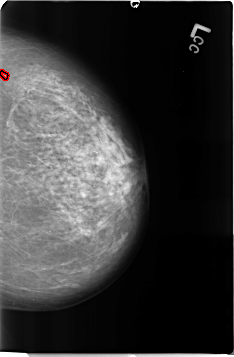

B_3361_1.LEFT_CC

FILE: B_3361_1.LEFT_CC.OVERLAY

TOTAL_ABNORMALITIES 1

ABNORMALITY 1

LESION_TYPE CALCIFICATION TYPE PUNCTATE DISTRIBUTION CLUSTERED

ASSESSMENT 3

SUBTLETY 2

PATHOLOGY BENIGN

TOTAL_OUTLINES 1

BOUNDARY